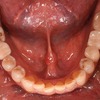

インプラント上部構造が完成しました。

上のリンクにあるように、私、とうとう両側第一大臼歯(2本)にインプラントをいれました。

向かって右側が奥から3番目、向かって左が奥から2番目です。

で、仮歯から最終補綴である上部構造にしたわけですが、まあ、本当になんでもバリバリ食べることができます。